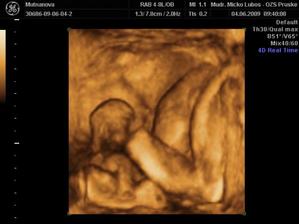

Naše druhé zlatíčko